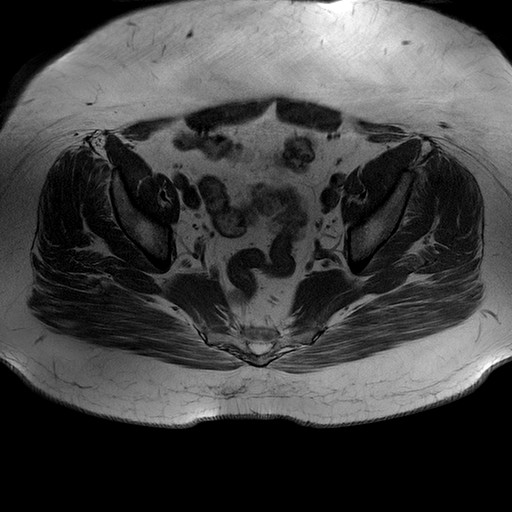

Esami: RMN BACINO

T1W_TSE

Evidenti e simmetriche alterazioni osteofitosiche in regione coxo femorale con riduzione delle rime articolari. Degenerazione completa del cercine glenoideo. Non attuali segni di versamento articolare. Non segni di edema osseo che escludono attuale algodistrofia od osteonecrosi. Lieve e simmetrica riduzione del trofismo della muscolatura glutea.